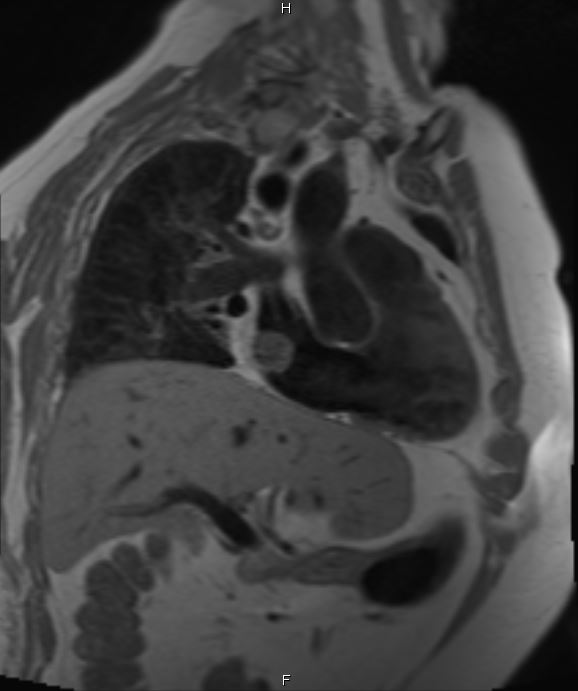

Cardiac MRI was performed on January 3, 2018, which revealed a large 2.5 × 2.9-cm lobular, fairly sessile mass in the right atrium. Without evidence of tissue destruction to suggest a malignant process, the lesion was suggestive of either myxoma or hematoma due to marked contrast uptake (which is seen less often with myxomas) (Figure 1).

Figures 1A-G. Cardiac MRI findings of a large, lobular, fairly sessile mass in the right atrium, measuring 2.5 x 2.9 cm, suggestive of either myxoma or hemangioma.